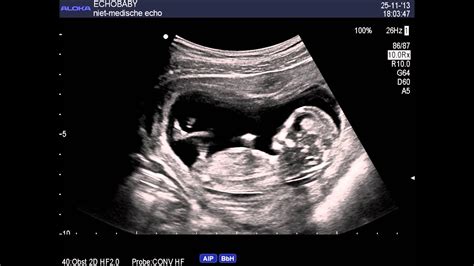

2Decho 13 weken jongen, met ingesproken uitleg YouTube

13 Weken Echo Jongen. 2D echofoto's jongen 13 weken zwangerschap YouTube Vanaf 12 weken gaan jongens en meisjes zich van elkaar differentiëren. Vanaf 12 weken gaan jongens en meisjes zich van elkaar differentiëren

We maken standaard bij elke zwangere een echo rond de 10-13 weken, de termijnecho Maar sommige, vaak ernstige, afwijkingen zijn wel al te zien Kan het geslacht veranderen na 13 weken? Zowel jongens als meisjes hebben voor de 13 weken een uitstekend geslacht

2D Echo 13 Weken Geslachtsbepaling Jongen, met ingesproken uitleg YouTube. Onze resultaten van de 13 weken echo's hebben we maanden lang vergeleken met dezelfde kindjes bij 16 weken De hoek is alleen bij jongens iets groter dan bij meisjes

13 Weken echo. De geslachtsbepaling is rond 13-14 weken juist makkelijker dan 16 weken Vanaf 12 weken gaan jongens en meisjes zich van elkaar differentiëren.